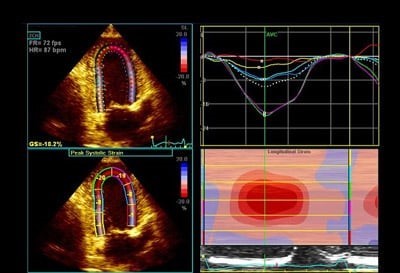

4. Parameters of longitudinal strain for each myocardial segment can be plotted on the bull’s eye and colour rendered, this can help quick evaluation and diagnosis.

Figure: Bull’s-eye plots of peak systolic strains (top panels) and segmental longitudinal strain curves (bottom panels) of the apical (A) 2- and (B, C) 4-chamber views. (A) Infarcted segments show reduced strain and post-systolic shortening (light blue, yellow). (B) Hypertrophic segments deform less (mid and basal segments). The apex might appear spared. (C) Amyloidosis shows frequently an apical sparing pattern. Colour labels of the segments in the bull’s-eye plots correspond to the strain curves. AVC = aortic valve closure; MVC = mitral valve closure